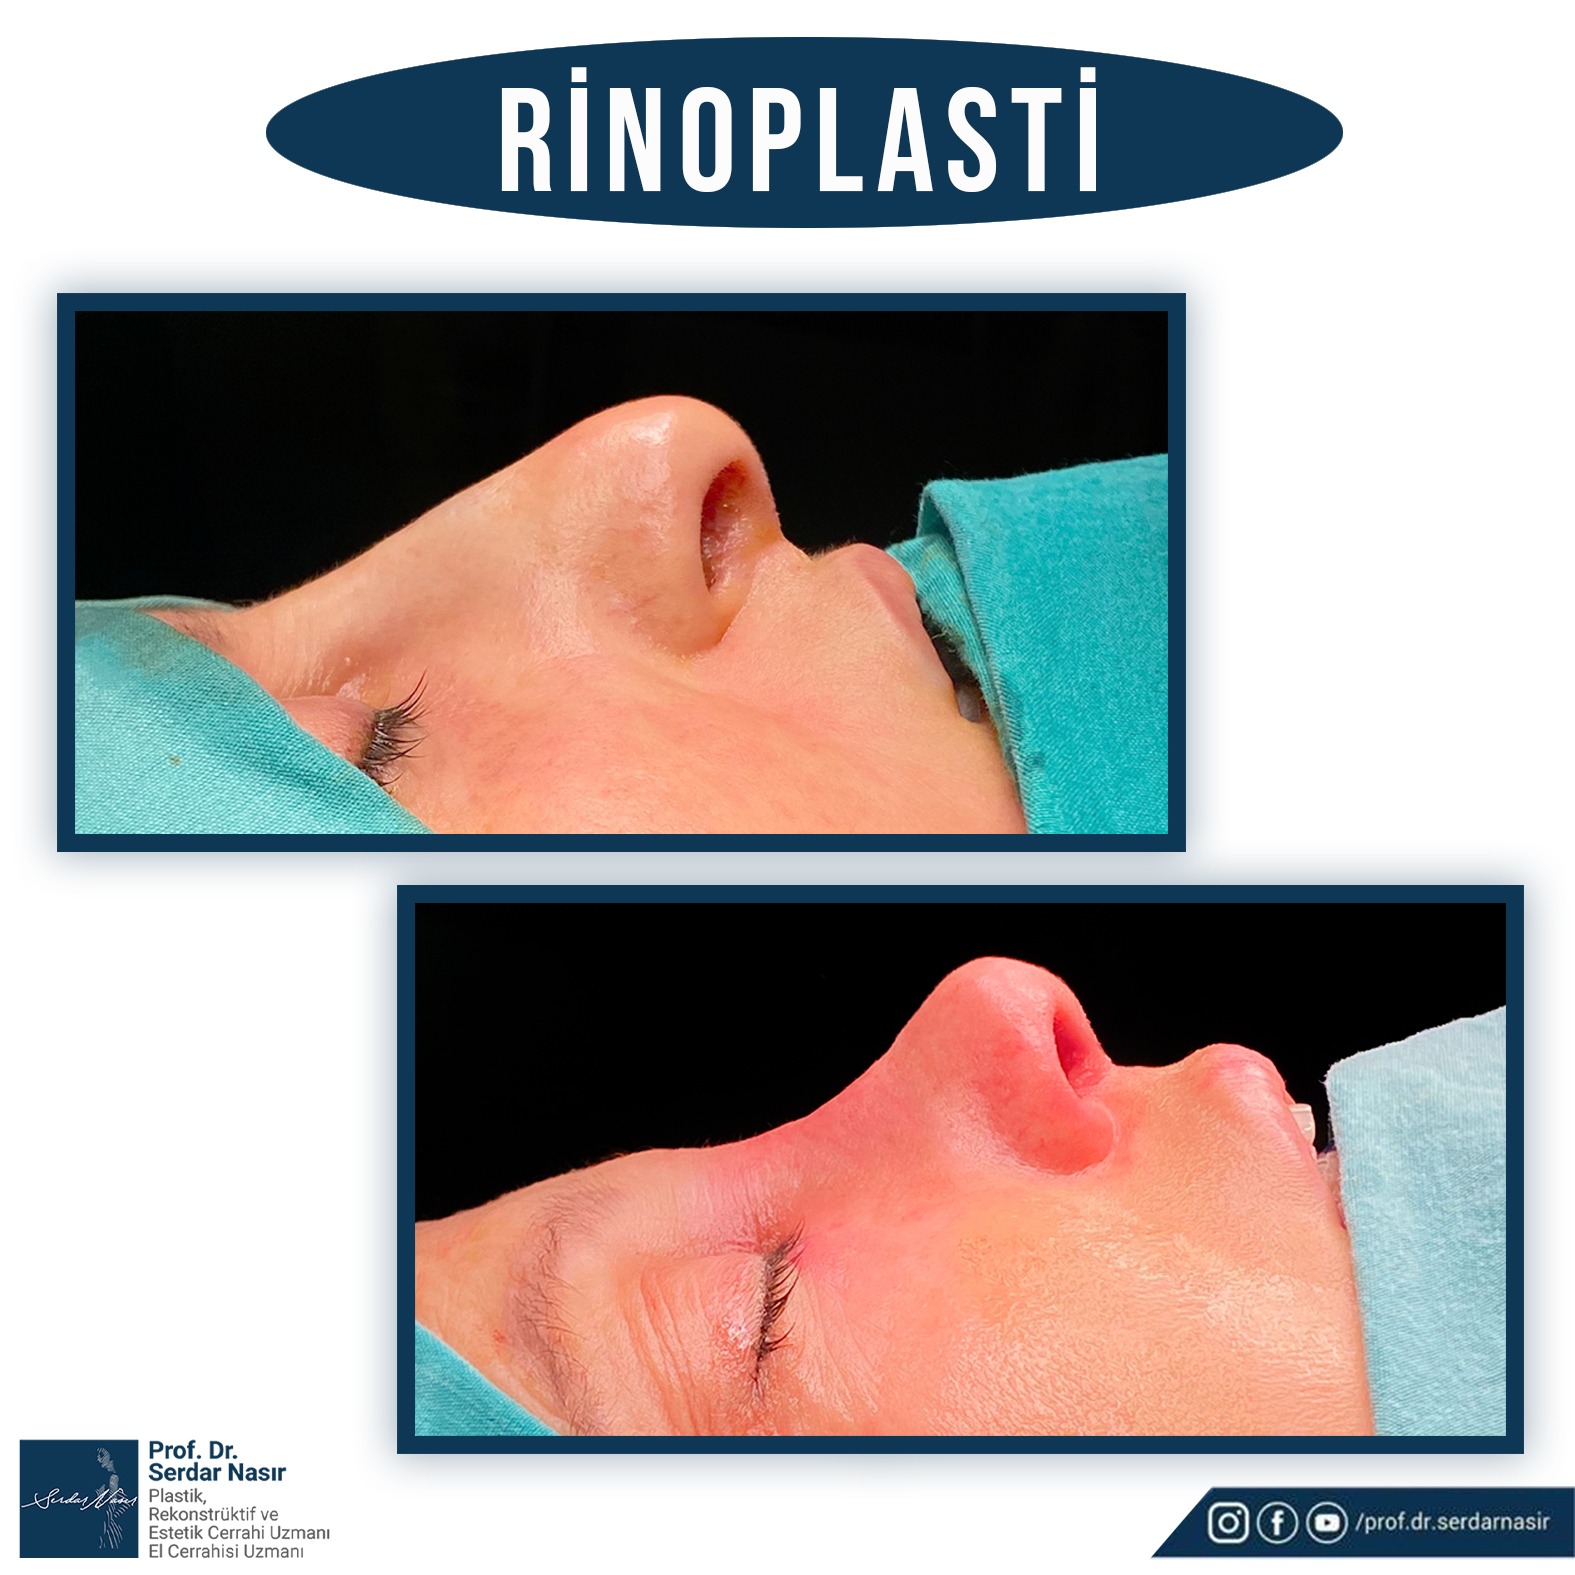

Estetik burun ameliyatı bana göre plastik cerrahinin en zor ameliyatlarından biridir. Çünkü burunda estetik olarak güzel bir sonuç elde etmeye çalışırken aynı zamanda fonksiyonel sonuçta yani hastanın nefes alıp vermesininde bozulmaması ve hatta sorun varsa düzeltilmesi gereklidir. Bu nedenle oldukça dikkatli yapılması gereken ameliyatlardır. Şu da bir gerçektir ki en çok revizyon dediğimiz ilk ameliyattan sonra tekrar bazı küçük deformitelerin veya hoşa gitmen bazı ayrıntıların düzeltilmesinin yapıldığı ikinci ve bazen üçüncü ameliyatlar en çok bu grupta saptanmaktadır. Bu nedenle özellikle ilk ameliyatın başarılı şekilde yapılması bu revizyon olasılığını azaltacaktır. Yine de estetik burun ameliyatı olmayı planlayan bir kişi her zaman için bir revizyon olasılığını akılda tutmasını öneririm.

Kişisel tecrübeme gelince ameliyat sonrası şişliklerin daha az olması, dokuları daha az travmatize etmesi gibi düşüncelerle ilk planda kapalı tekniği tercih etmekteyim. Ancak hastanın burun deformitesi özellikle burun ucuna yönelik ağırlıktaysa veya çok detaylı bir cerrahi girişim yapılacaksa açık tekniği tercih etmekteyim. Ancak tecrübelerime göre kapalı teknik ile açık tekniğe gerek kalmadan bir çok hastanın sorunu çözülebilmektedir.

Septumdeviasyonu ve ona ikincil teşkil edebilecek konka büyümesi nefes alma sorununun başta gelen nedenlerindendir. Bu bozukluğun düzeltilmesi zaman zaman estetik ameliyatlara eşlik eder zaman zaman ise hastalar sadece bu sorunla başvururlar. Eğer estetik ameliyatla birlikte yapılacaksa estetik kaygılar ön planda tutularak septum ve konka cerrahisinin ikinci plana alınması nefes zorluklarına ameliyat sonrasında da devam etmesine ol açabilir. Sadece bu sorunla gelmiş hastada ise zaman zaman bu cerrahi sonrası burunda bazı estetik sorunlar oluşabilir. Bu nedenle estetik ve fonksiyonel harmoninin hastalarda çok iyi sağlanması gereklidir.